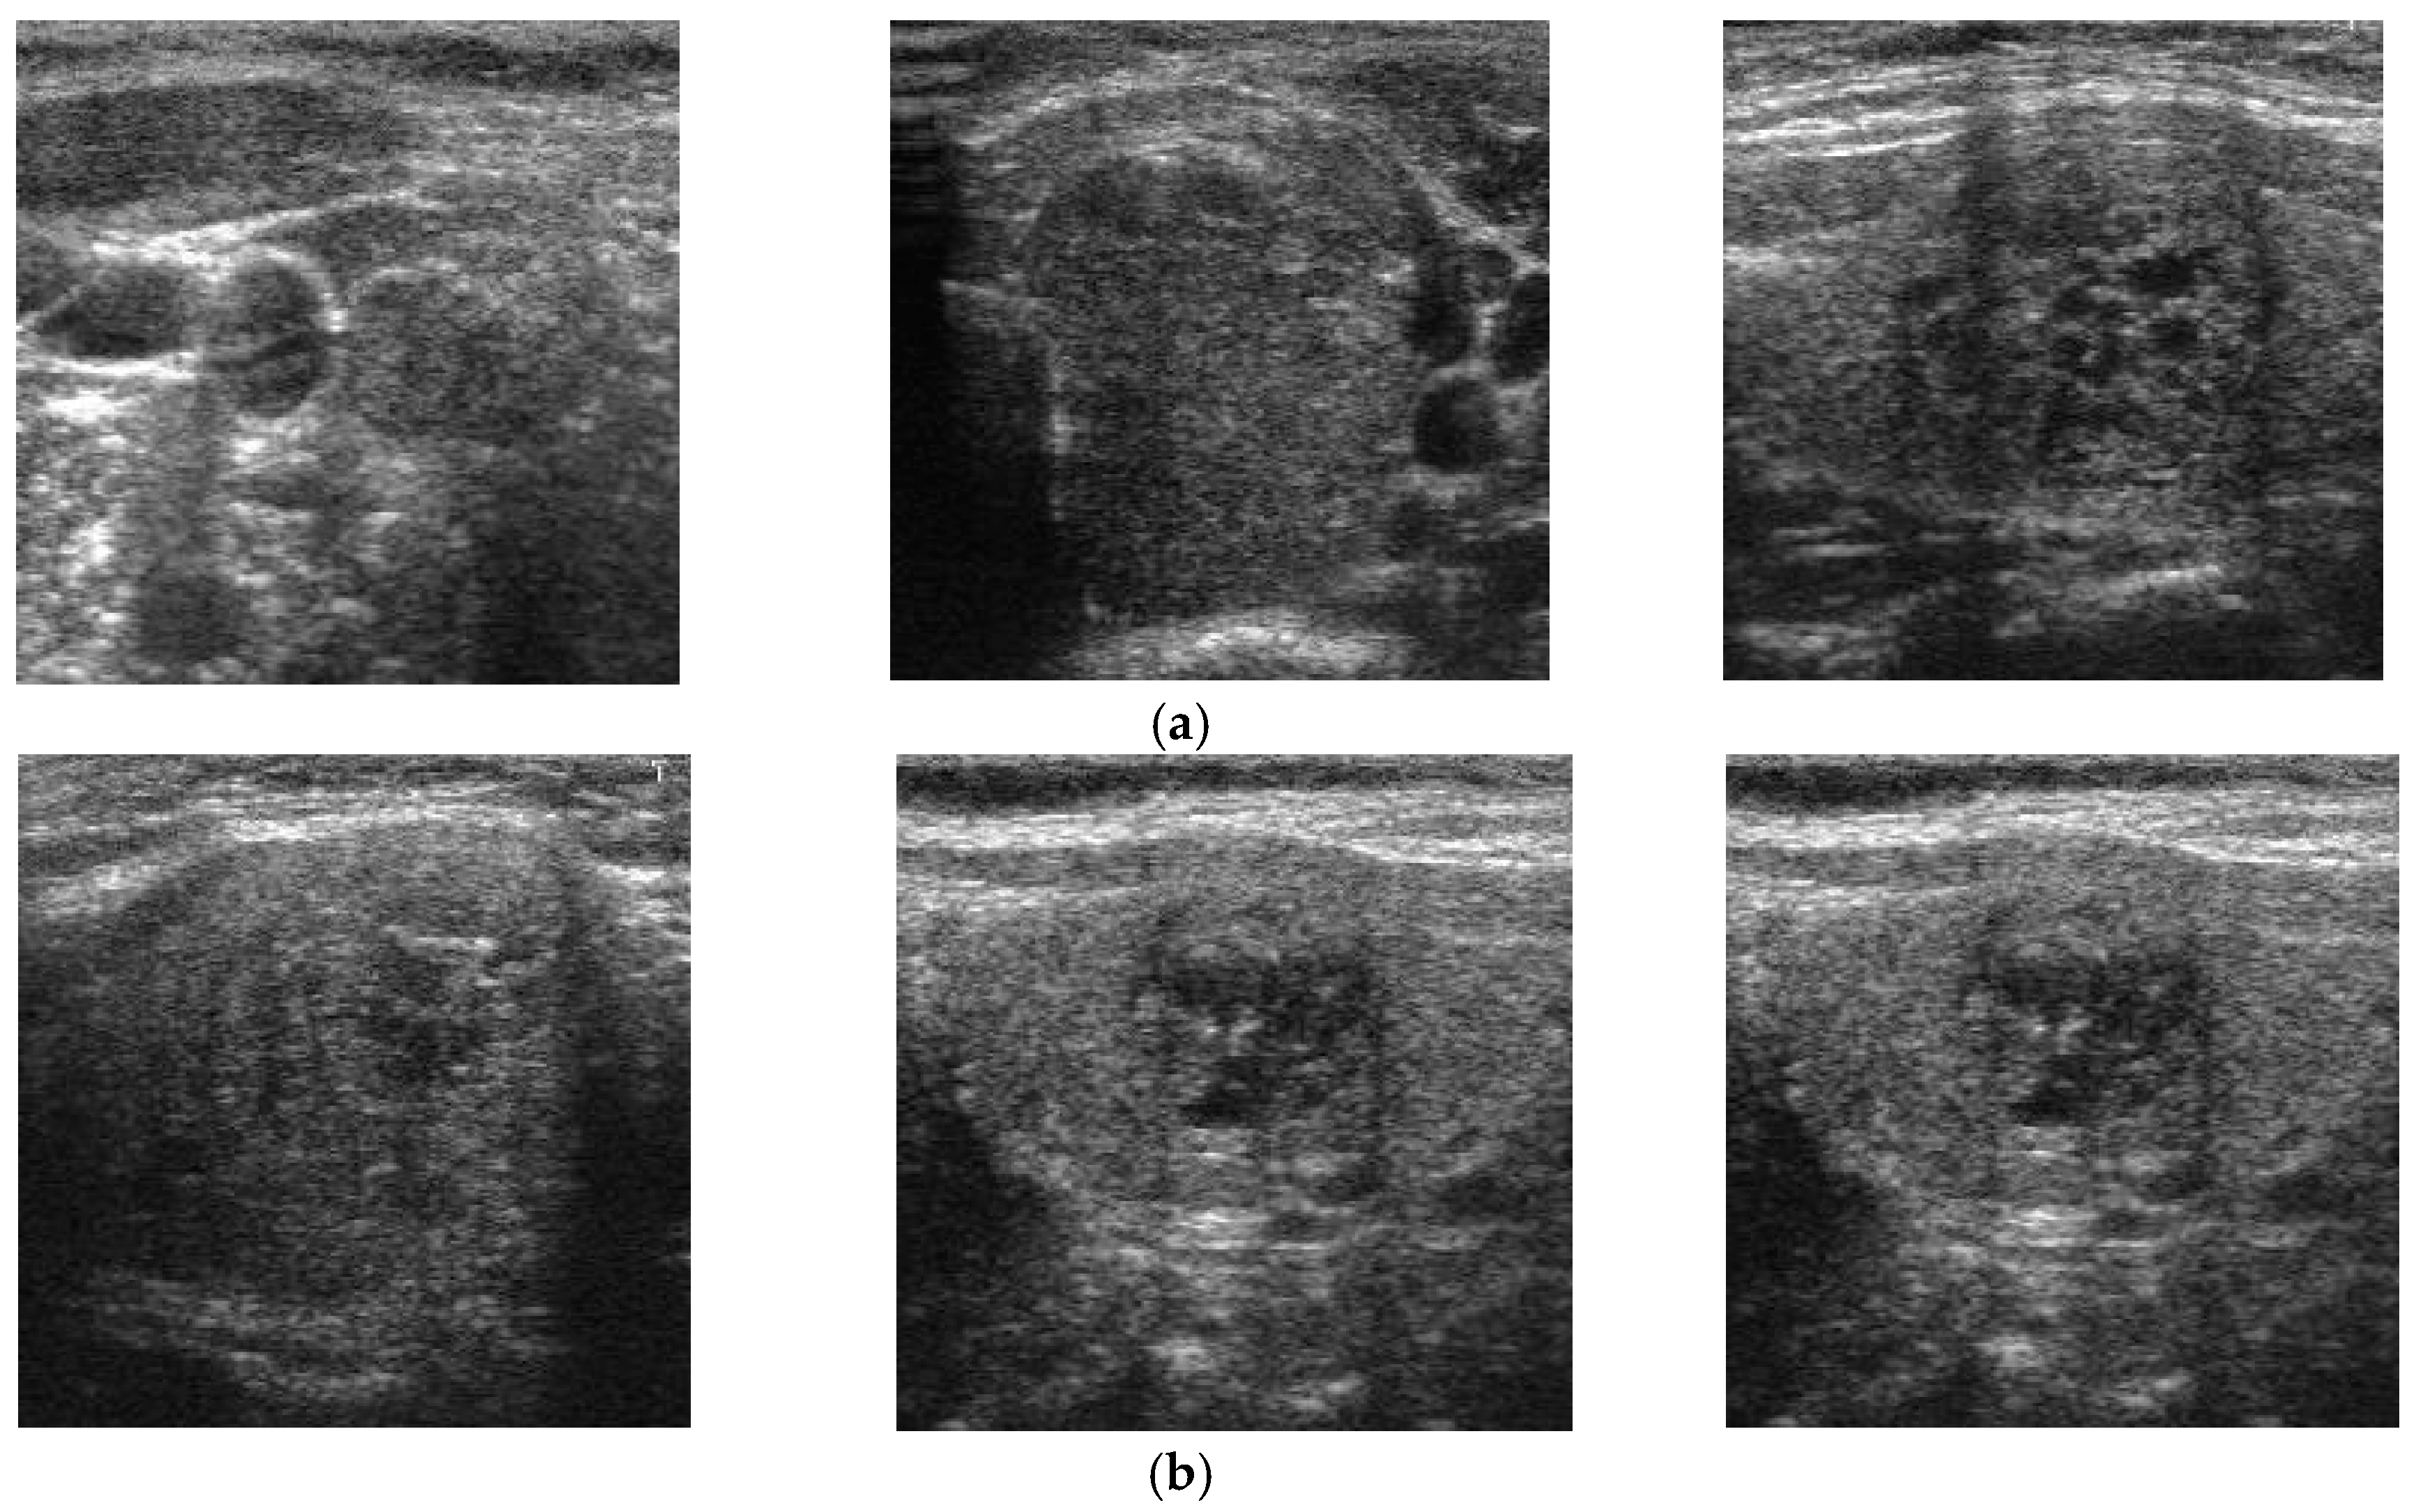

To demonstrate the efficiency of our proposed method, Figure 13 shows some examples of correct classification results using our proposed method. In this figure, Figure 13a shows some classification results of benign case images and Figure 13b shows some classification results of malign case images. The benign case images in Figure 13a seem to contain nodules by the appearance of round-shaped textures of different sizes. As a result, they are hard to recognize as benign case images by human perception, based on experience. However, they were correctly classified as benign case images by our proposed method. In contrast to Figure 13a, b presents some ground-truth malign case images. As shown in this figure, it is hard to recognize these images as malign case images by human perception, because the appearance of nodules is not clear, due to the small size of the nodules. By inputting these images to our proposed method, we correctly recognized them as malign case images. Based on this result, we conclude that our proposed method is sufficient for classifying ultrasound thyroid images into benign and malign classes. Also, it can provide valuable suggestions to medical doctors in diagnosing thyroid nodules using ultrasound images.

In Figure 14, we presented some examples of error cases obtained with our proposed method using the TDID dataset. Figure 14a shows some errors for a benign case, in which the proposed method incorrectly classified a benign case as malign, and Figure 14b shows errors for a malign case in which the proposed method incorrectly classified a malign case as a benign case. As shown in Figure 14a, although the images are benign, they contain several features that normally appear in the malign cases, such as the circle shape nodules, with a high illumination that makes them look like the malign nodule with calcification phenomenon. Consequently, they were incorrectly classified as malign. In Figure 14b, although the images are malign cases, the nodules are small and do not appear clearly distinguishable from benign cases. Due to this problem, they were incorrectly classified as benign cases. Through this example and the experimental results of our study and previous studies, we can see that the primary problem with the thyroid nodule classification system is data for training the classification model. As shown in previous studies [28,32], the CNN-based classification method works well when the networks were trained using a large dataset (combination of several datasets). Although our proposed method produced better classification results than previous studies with the same dataset (TDID dataset), its performance can be better if it is trained using a large dataset. In our future research, we will investigate this condition using a large dataset.

Figure 13. Examples of correct classification result using our proposed method using (a) benign case images which are similar to malign case images; and (b) malign case images which are similar to benign case images.

Figure 14. Example of error cases using our proposed method with the TDID dataset (a) benign-to-malign error cases, and (b) malign-to-benign error cases.